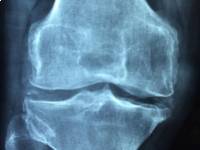

Emellett még ott van a csontritkulás kialakulásának kockázata, ha túl sok koffeint viszünk be a szervezetünkbe. Amióta tudjuk, hogy a koffein kalcium kiválasztódást okoz a vizeletben, lehetséges, hogy ez is hozzájárul a csontritkulás kialakulásához. Ha folyamatos a pajzsmirigy túlműködése, vagy Basedow-kór áll fenn Önnél, akkor a kockázat még magasabb és ez is egy újabb ok arra, hogy óvatosabban fogyasszuk ezeket a koffein tartalmú italokat.